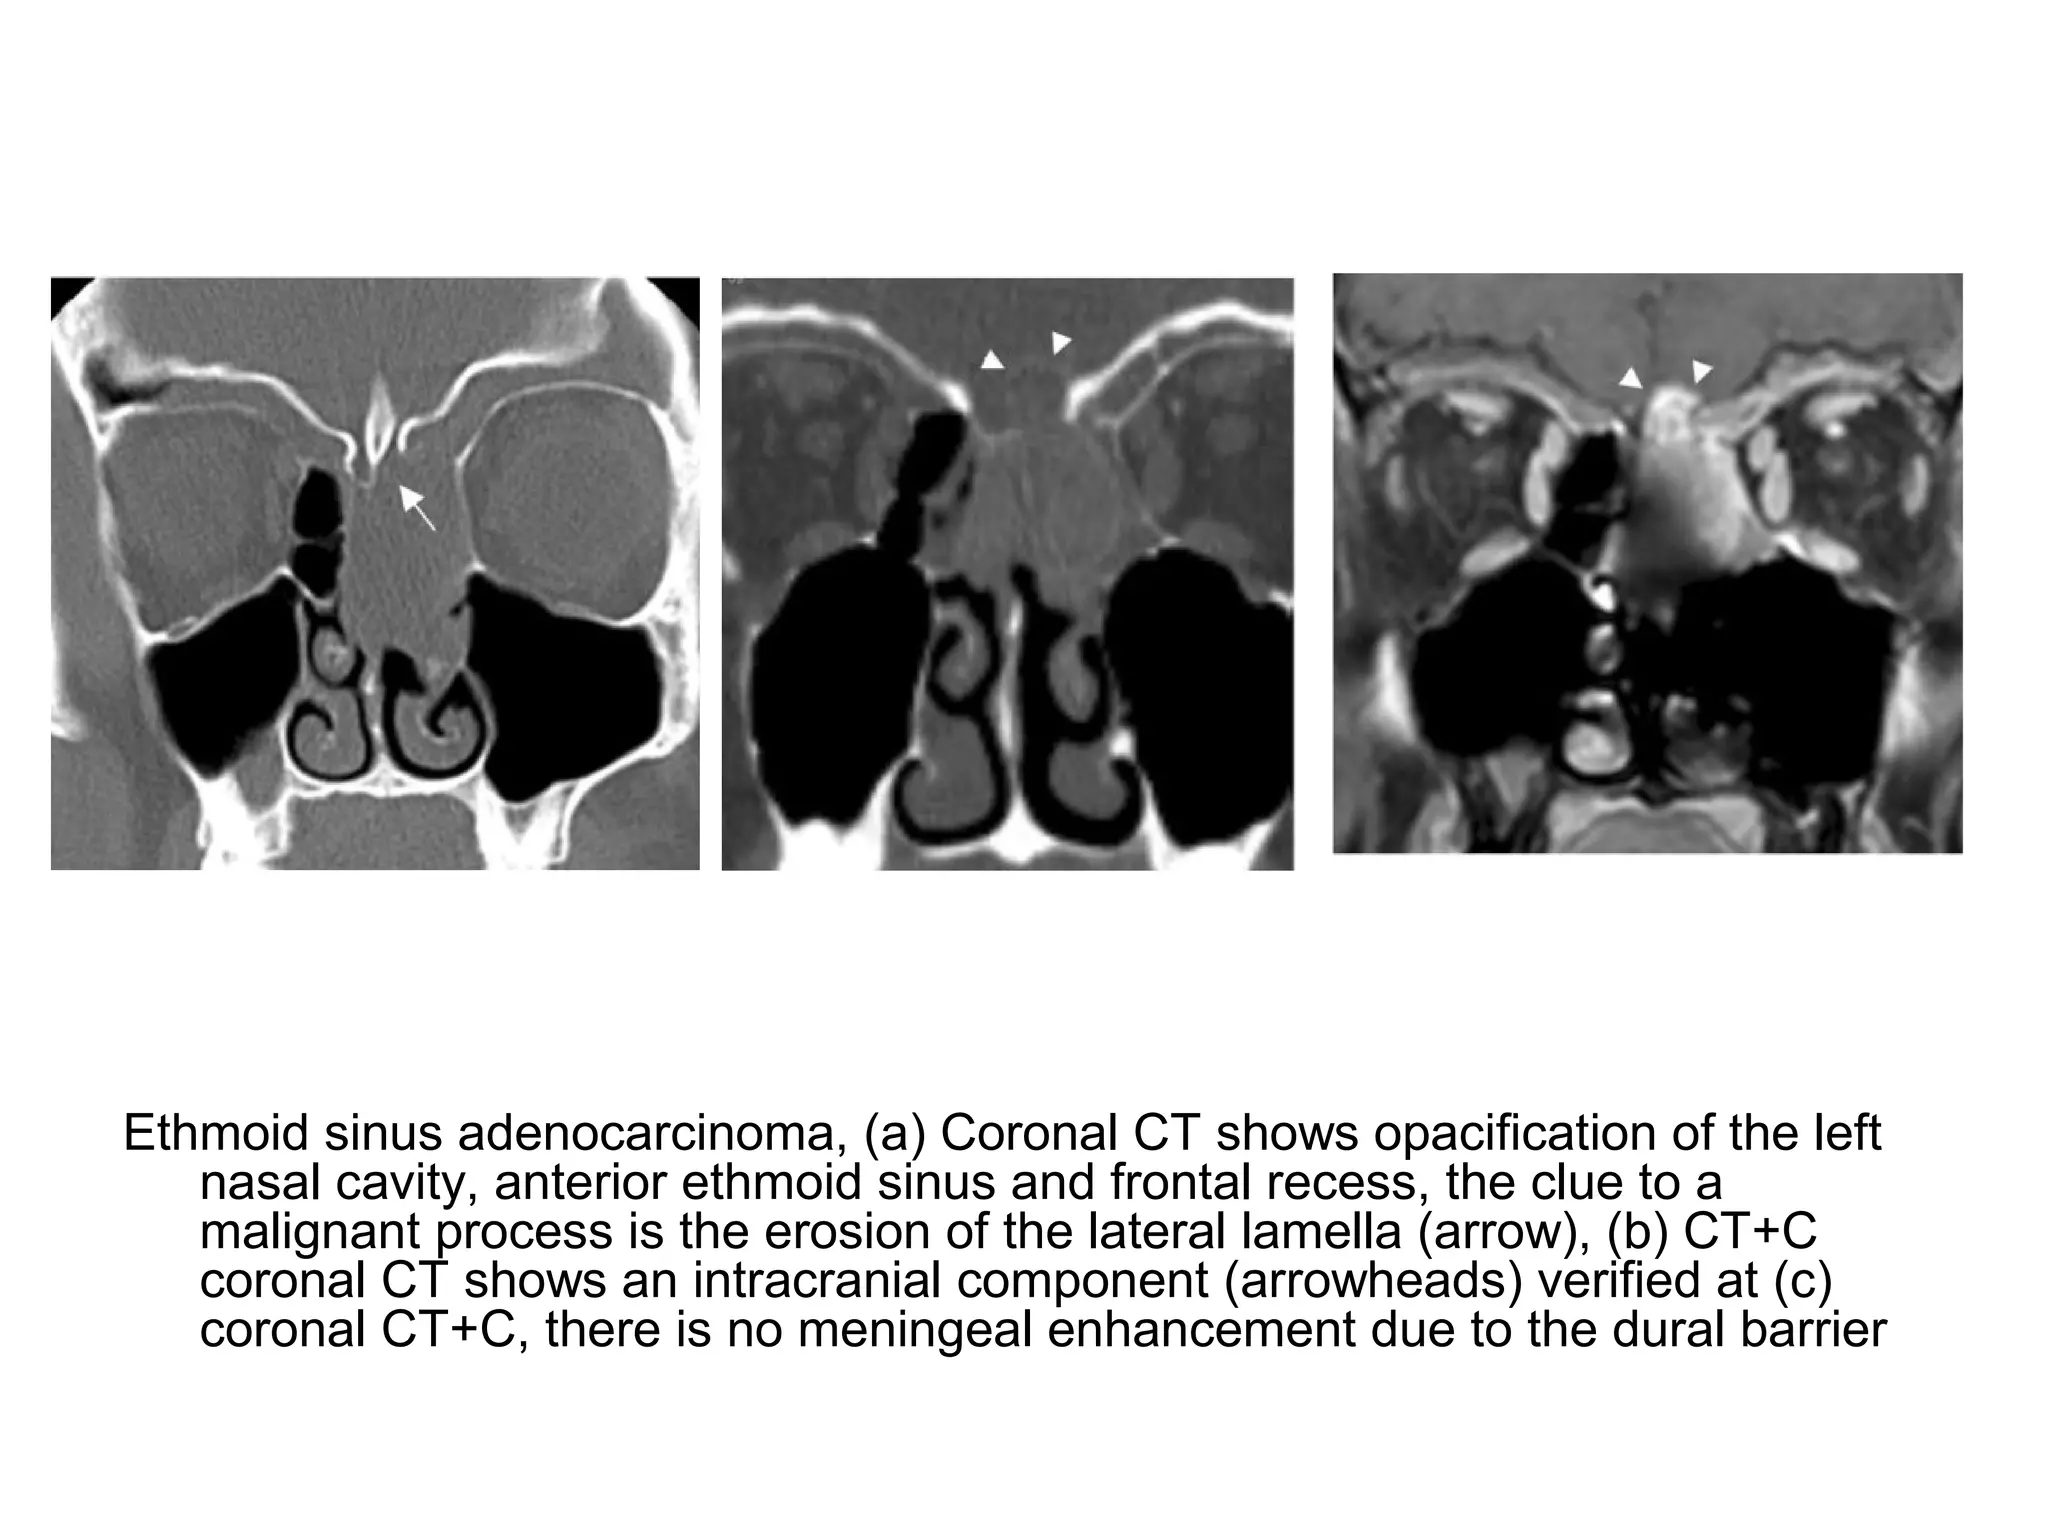

Ethmoid sinus adenocarcinoma, (a) Coronal CT shows opacification of the left

nasal cavity, anterior ethmoid sinus and frontal recess, the clue to a

malignant process is the erosion of the lateral lamella (arrow), (b) CT+C

coronal CT shows an intracranial component (arrowheads) verified at (c)

coronal CT+C, there is no meningeal enhancement due to the dural barrier